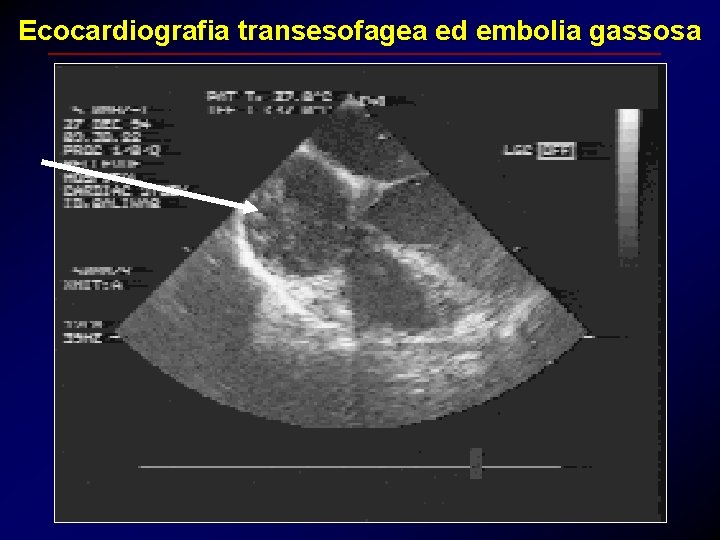

Ecocardiografia transesofagea ed embolia gassosa